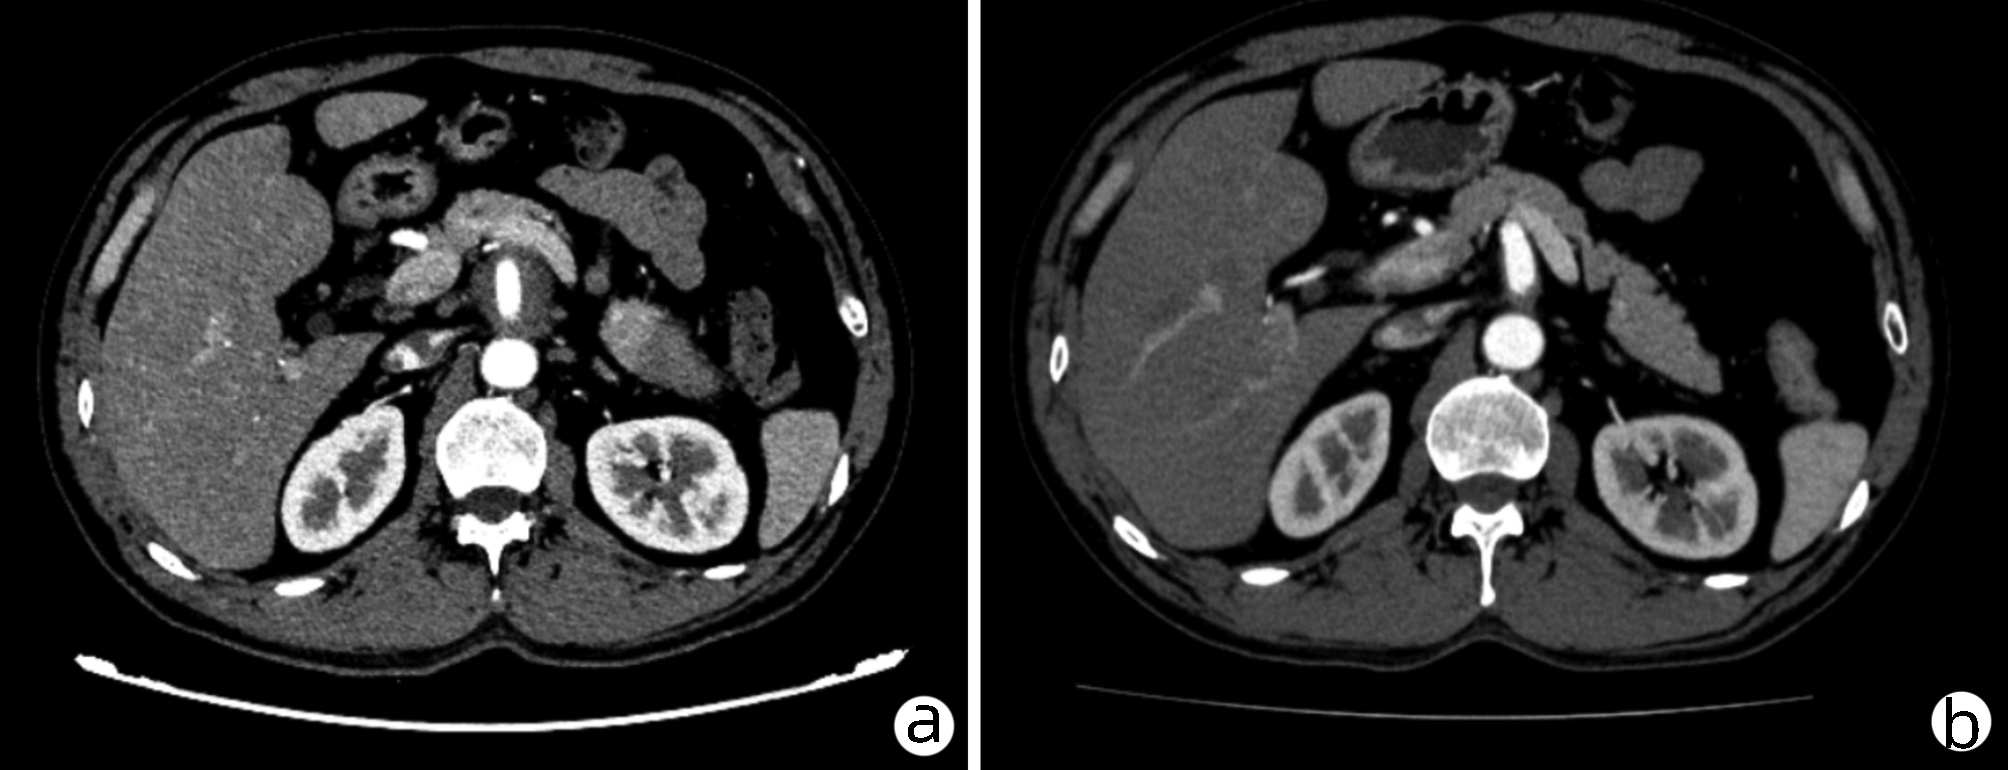

Spontaneous rupture of biliary dilatation with cancer: A case report

Xiaotong QIU, Zhengqi WU, Yushi CAO, Xuxiang XIA, Guoyue LYU

2022, 38(5): 1129-1130. DOI: 10.3969/j.issn.1001-5256.2022.05.031

Abstract(907) HTML (321) PDF (2537KB)(30)

Abstract: